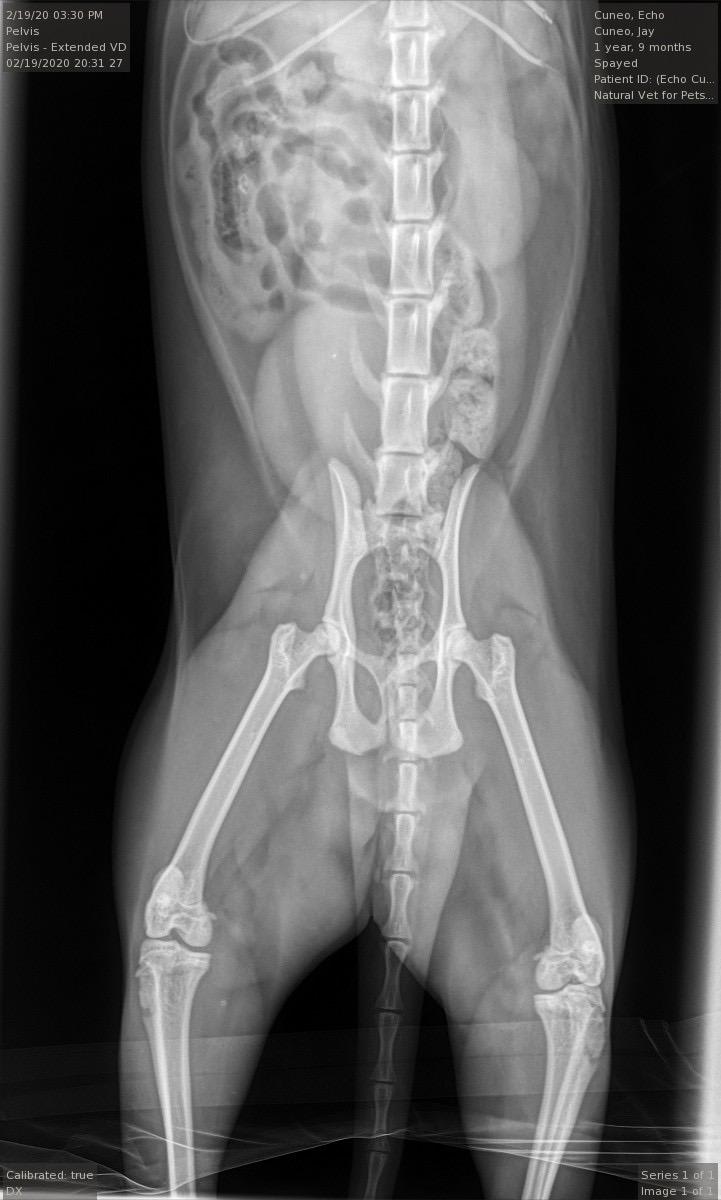

Pet's info: Cat | Mixed Breed | Female | spayed | 1 year and 10 months old | 9.5 lbs

My cat seemed to hurt her leg somehow this morning and was growling/hissing/didn’t want food. Vet sedated her to X-ray/examine. Said nothing broken and felt alright she may have just sprained. She has buprenorphine for pain next few days. Do her x rays indeed look normal and ok from what can be seen in X-ray? No swelling, but definitely still painful as initial drugs wore off at home. Just gave tonight’s oral buprenorphine dose

Hi, there is no evidence of any fractures on the pictures of these X-rays. Is Echo on any antinflammatories ? I often find cat bites can be painful even when superficial, is Echo allowed outside ? As this is all recent, it is likely that you need to give Echo some time to get better. Within 3-4 days with rest, pain relief she should go back to her normal self. If Buprenorphine is helping but just for a short period of time, I would enquire about having additional pain relief in terms of antinflammatories . This is provided that Echo is otherways healthy and does not have any other health concerns. Hope she gets better soon !